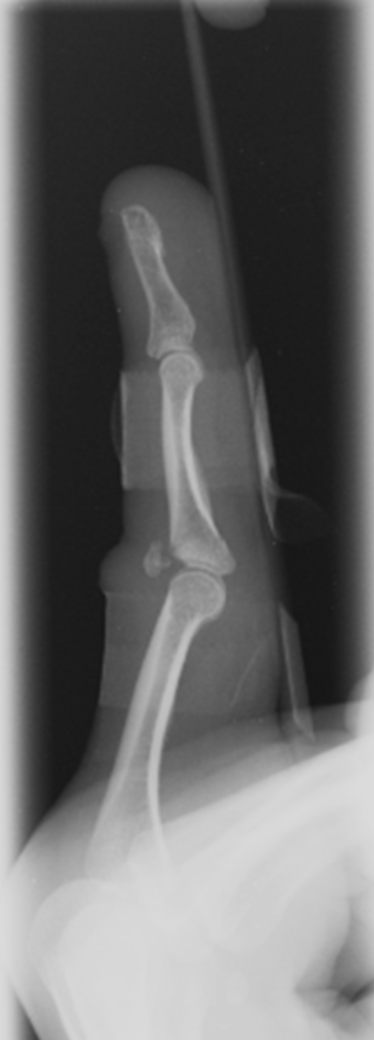

The patient “jammed” her finger playing basketball. What is the specific diagnosis?

dorsal plate fracture